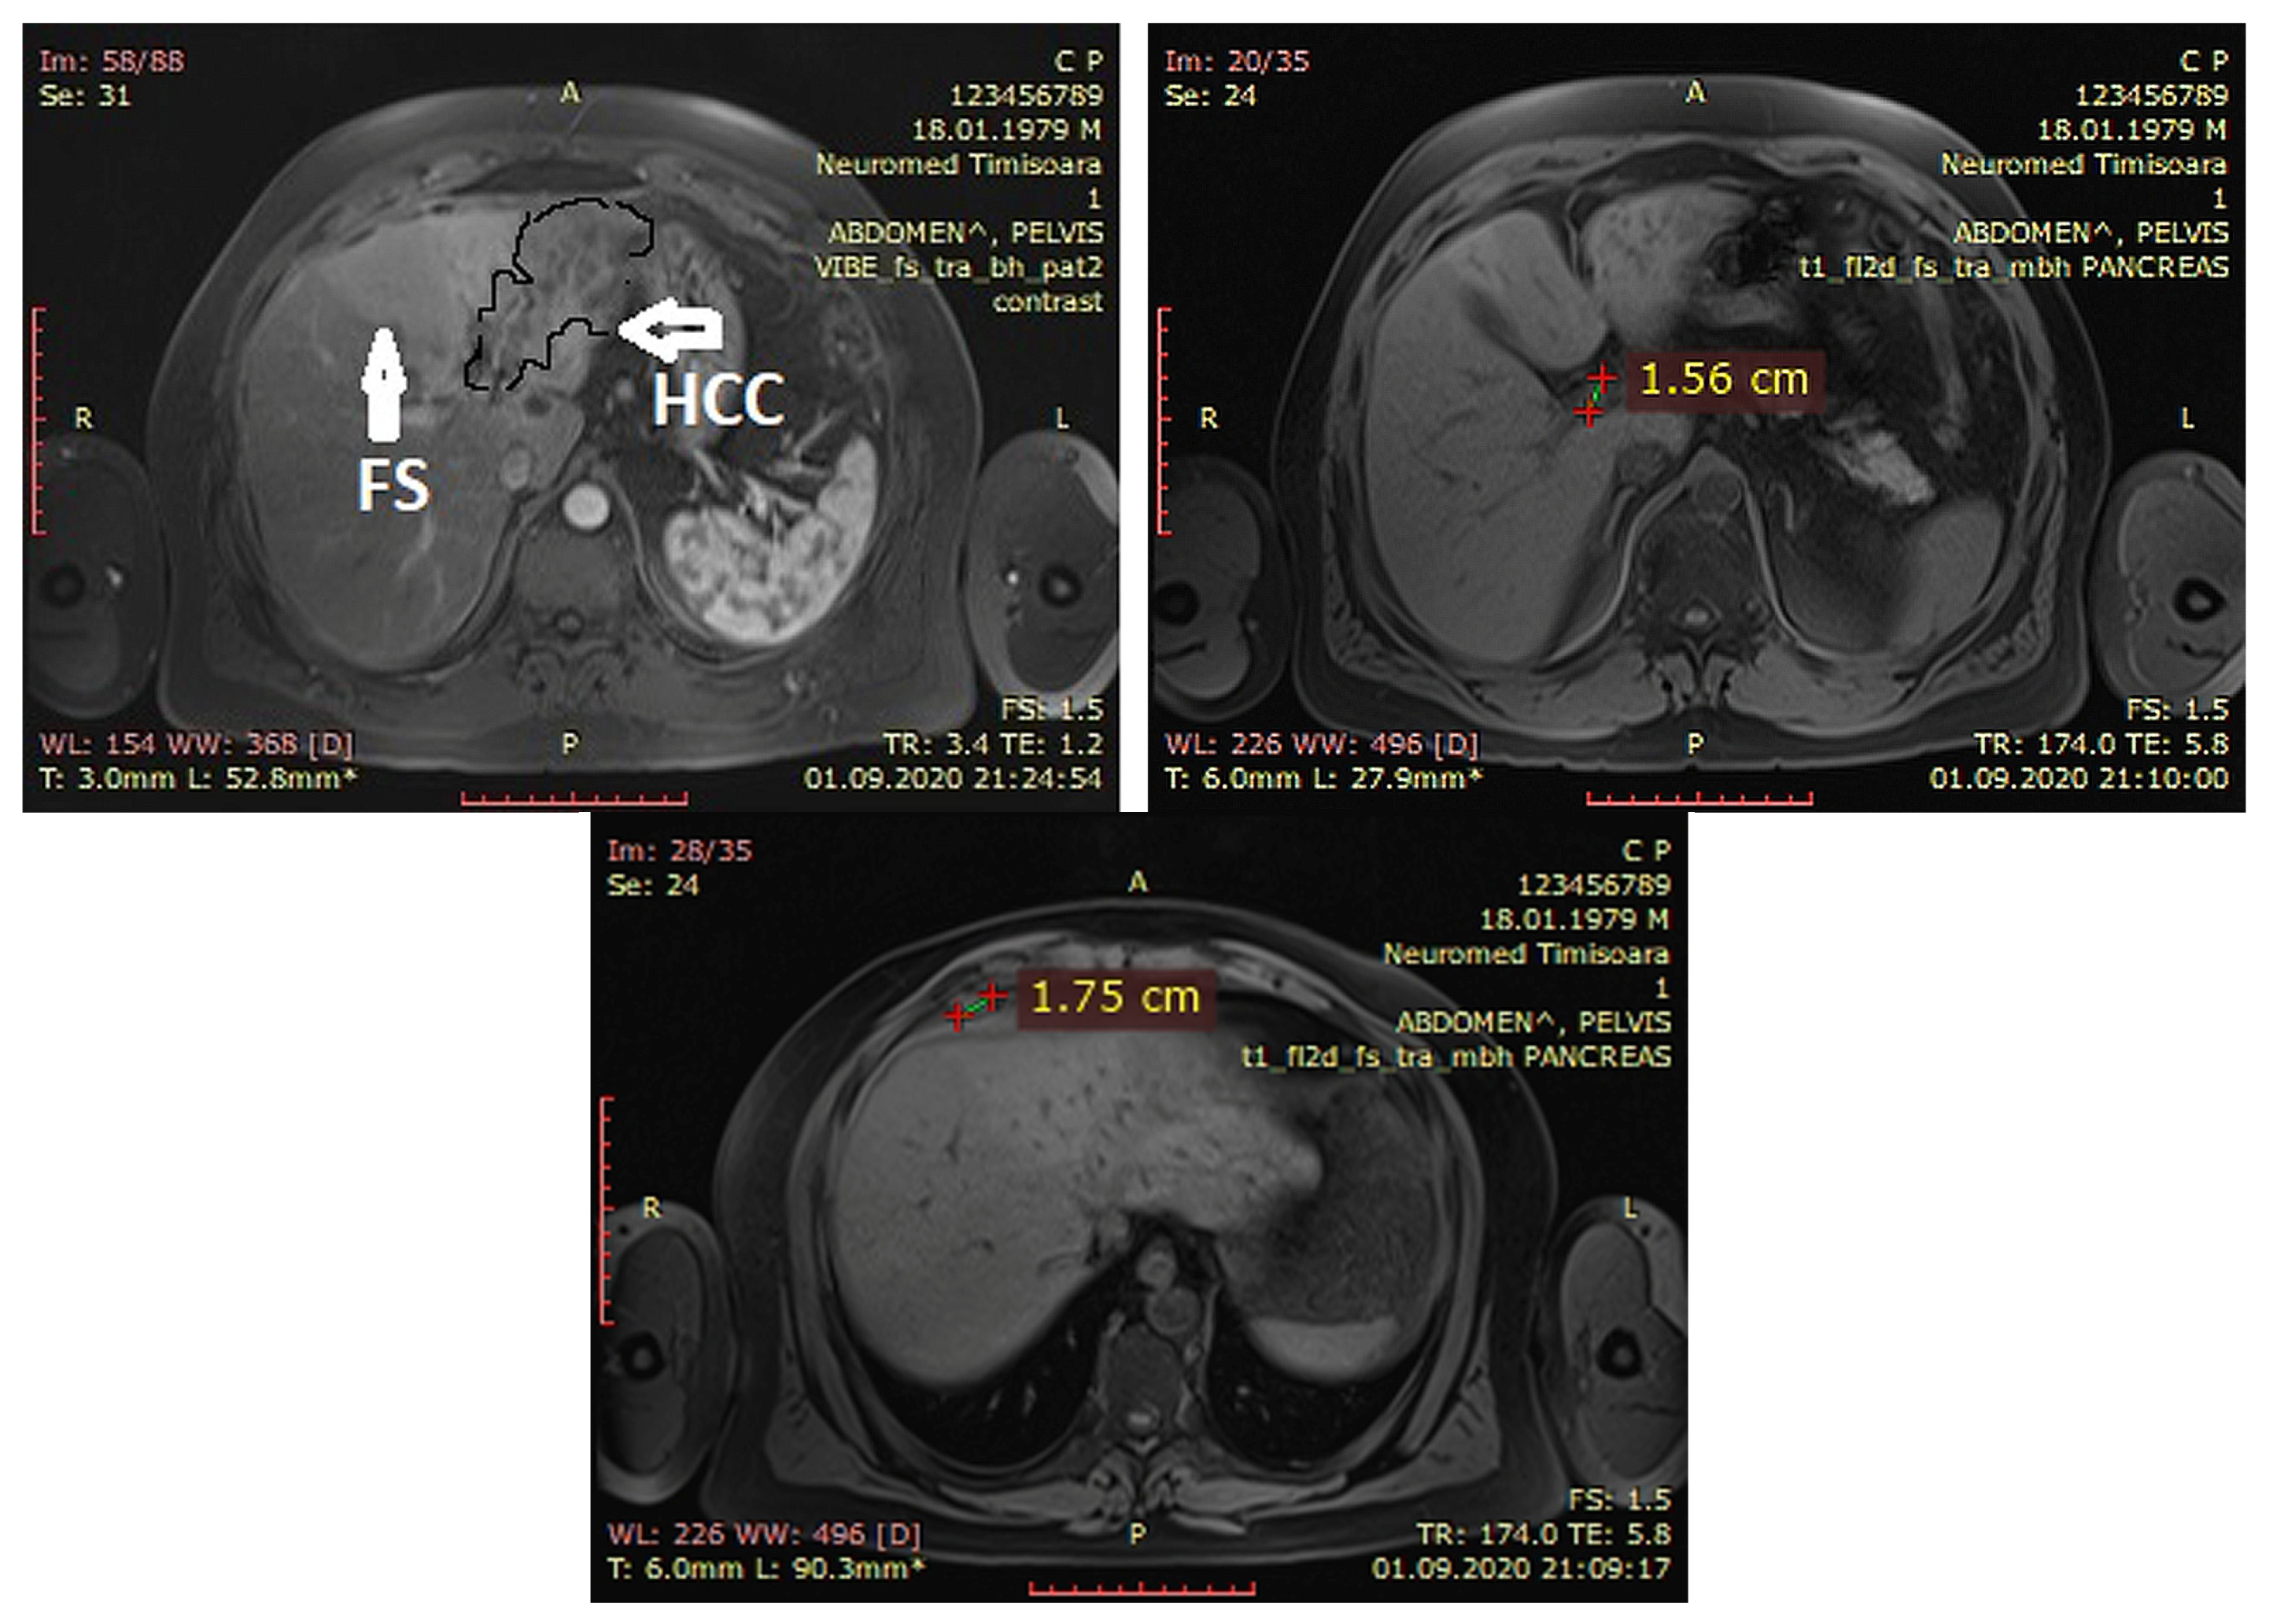

2. Case Report